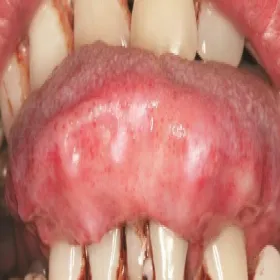

Amyloidozy skóry język

Amyloidoza skóry